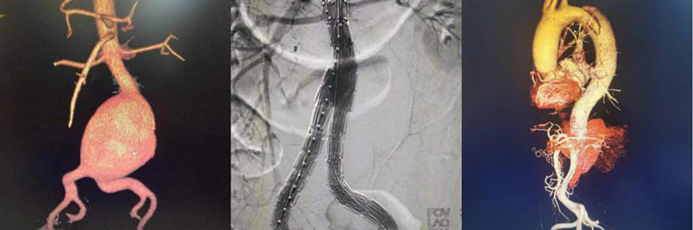

血管疾病专业组:常规开展主动脉夹层的腔内手术、胸主动脉瘤、腹主动脉瘤的腔内手术和开放手术、颈动脉内膜剥脱和支架置入手术、肝硬化、门静脉高压症断流、脾肾静脉及门腔静脉分流、下肢动脉闭塞症、深静脉血栓形成、糖尿病足、血栓闭塞性脉管炎、动脉栓塞等疾病的外科血管旁路搭桥,血管成型,静脉动脉化,球囊导管取栓,腔静脉滤器植入,肠系膜静脉血栓形成经股动脉穿刺肠系膜上动脉持续溶栓治疗,大、小隐静脉曲张微创手术,下腔静脉、股动脉等血管损伤的救治。并成功开展目前最前沿的高难度主动脉弓三开窗腹膜分支支架置入术。

腹主动脉腔内隔绝术

胸主动脉开窗、覆膜支架置入术